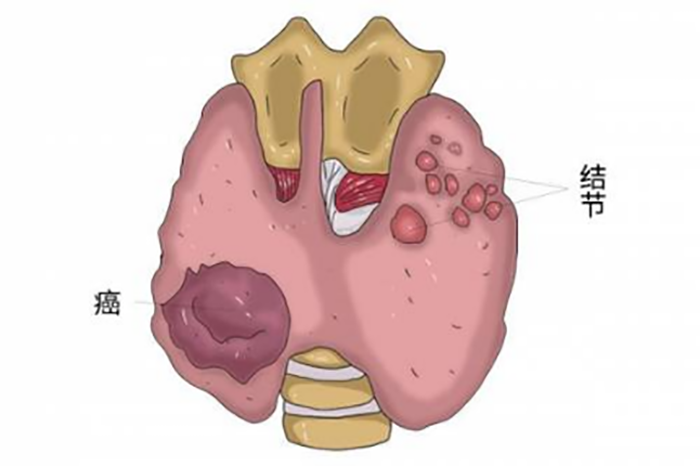

甲状腺是颈部正中偏下的一个蝴蝶状器官,主要功能是分泌甲状腺激素,在人体代谢等方面发挥重要作用。

甲状腺结节是甲状腺细胞的异常生长产生的“肿块”,可能是单个,也可能是多个。

绝大多数情况下,超过90%的甲状腺结节是良性的,只有5%-15%的甲状腺结节为恶性,即甲状腺癌。